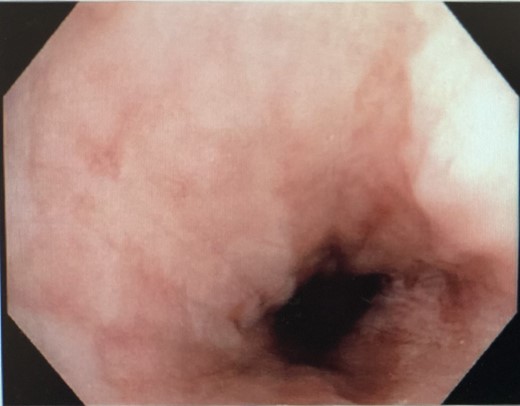

He was commenced on high-dose PPI, IV Antibiotics and analgesia. Emergency gastroscopy showed middle third of esophagus consistent with esophagitis and circumferential ischemia/necrosis in distal esophagus 27–34 cm (Fig. 6). Mucosal biopsies taken revealed ulcerated squamocolumnar mucosa with necrosis and inflammation. No CMV inclusions were identified.

Nasojejunostomy tube was inserted and feeds were commenced. Interval gastroscopy in 2weeks revealed superficial sloughing of esophagus from 27 to 34 cm consistent with partial thickness esophageal necrosis (Fig. 7). Clear fluids were commenced and gradually upgraded to full diet over the course of 6 weeks. Follow-up gastroscopy at 9 weeks showed completely healed mucosa (Fig. 8).

Interval endoscopy at 2 weeks showing signs of healing (Superficial slough at the area of partial necrosis).